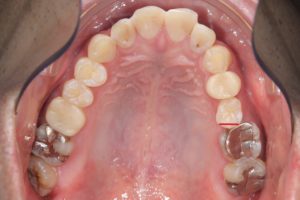

以下一例。

左上第二小臼歯頬側を赤い線で示す。